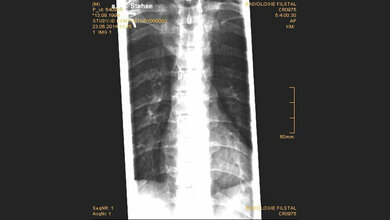

Im Mittelpunkt der Tagung stehen insbesondere Fragen nach den Ursachen und Risikofaktoren möglicher Komplikationen. „Entscheidend hierfür ist der Verlauf von systemischen Entzündungsreaktionen. Diese werden bestimmt durch die komplexen Wechselwirkungen zwischen verletztem Gewebe, Immunsystem, Kreislauf und Psyche“, erklärt Professor Florian Gebhard. Der Leiter der Klinik für Unfall-, Hand-, Plastische und Wiederherstellungschirurgie ist Sprecher des SFB und gehört zu den Organisatoren des Symposiums. Mit den wissenschaftlichen Erkenntnissen, die die Ulmer Traumaforscher bei der Tagung vorstellen, wollen sie etwas mehr Licht in diese komplizierten molekularen und zellulären Zusammenhänge bringen. Hinzu kommen zahlreiche Hauptvorträge renommierter Wissenschaftler aus dem Ausland, die als Keynote Speaker Einblicke geben in den aktuellen Stand der Forschung.

Das Programm ist unterteilt in drei Themenblöcke. Der erste Abschnitt zum Thema „Gefahrenantwort“ behandelt zum einen molekulare Signalgebungsprozesse, die an der Steuerung von Entzündungsprozessen beteiligt sind sowie die zelluläre Reaktionen des Immunsystems. Der zweite Themenblock behandelt Begleiterkrankungen wie Atherosklerose oder Adipositas und hinterfragt, wie sich diese auf Krankheitsverläufe und Wundheilungsprozesse auswirken. Im Fokus stehen hier zudem individuelle Risikofaktoren wie das Rauchen und der Konsum von Alkohol. Der dritte Tagungsteil befasst sich mit dem Thema Geweberegeneration und stellt aktuelle Forschungsergebnisse über Heilungs- und Reparaturprozesse in Knochen-, Haut- und Nervengeweben vor.

„Um die Versorgung und Therapie von Traumapatienten verbessern zu können, ist es wichtig, dass neue Forschungsergebnisse so schnell wie möglich den Weg aus dem Labor in die Klinik finden“, meinen auch die stellvertretenden SFB-Sprecher Professor Markus Huber-Lang und Professorin Anita Ignatius, die ebenfalls zum Tagungskernteam gehören. Die Podiumsdiskussion am Ende der Tagung befasst sich daher mit den klinischen Implikationen der Forschung und gibt ganz konkrete Einblicke in die medizinische Praxis, beispielsweise bei der Behandlung von Sepsis, die umgangssprachlich auch als „Blutvergiftung“ bekannt ist. (idw, red)